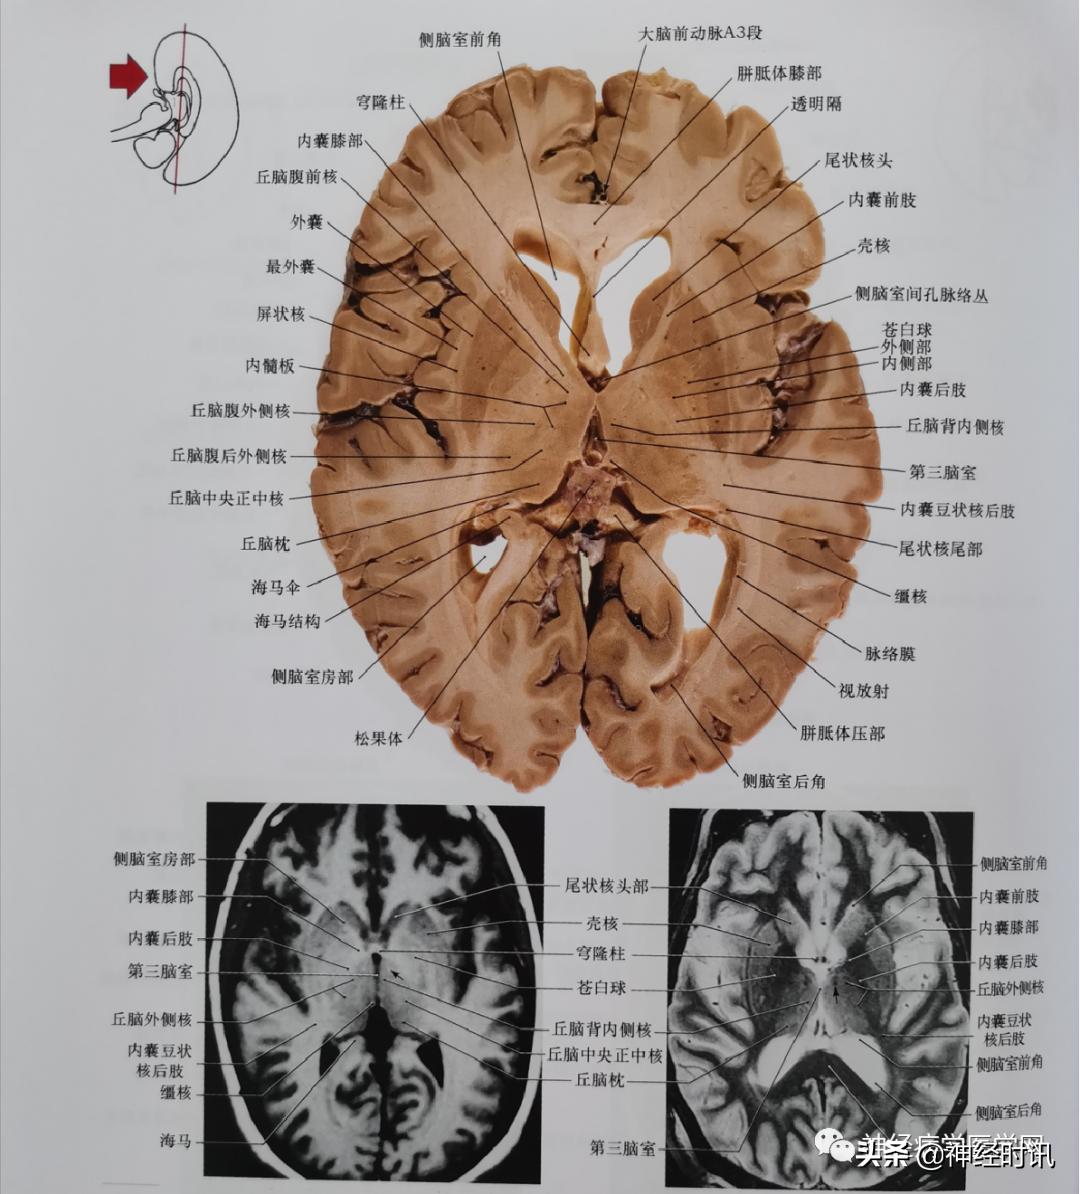

图9 通过胼胝体压部、侧脑室后角及小脑,包括部分小脑外侧核平面的冠状位影像。此平面亦通过侧脑室三角区。

图10 通过豆状核、内囊的前后肢、丘脑的主要核团、第三脑室和松果体平面的轴位影像。苍白球的中间和侧方部分在左侧的轴位切片上清晰可见。在两张MRI上箭头都指向乳头丘脑束,这两张片子为相同平面MRI影像(左T1 右T2)。